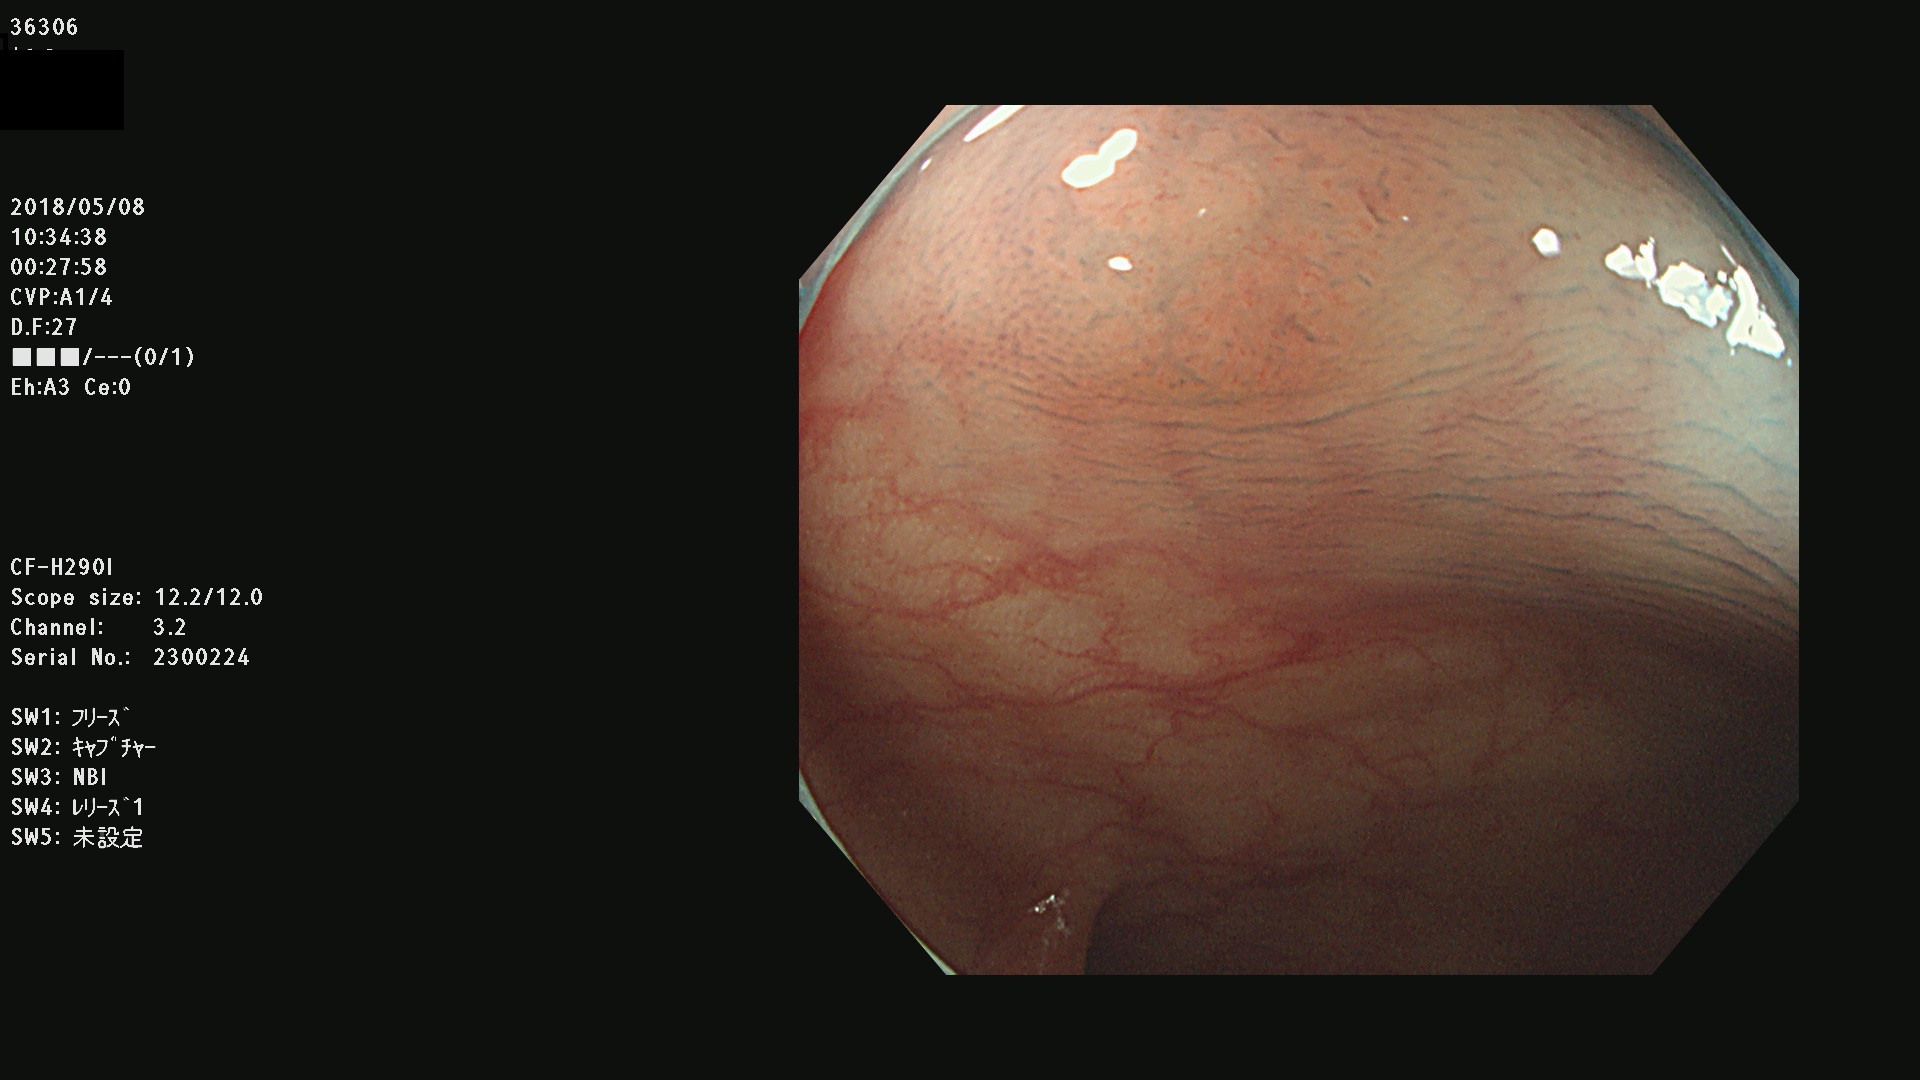

発見困難で危険性の高い平坦型病変(上記100名より抽出) ![]()